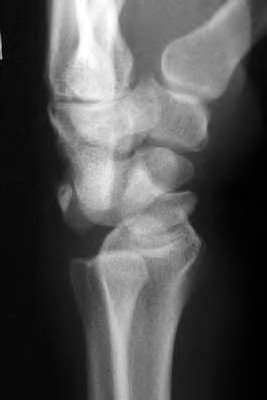

The Lisfranc ligament is the strongest ligament in the tarsometatarsal joint complex. It courses obliquely from the lateral aspect of the medial cuneiform to the medial base of the second metatarsal. It acts as the primary stabilizer of the second metatarsal base. Disruption results in the classic widening between the first and second rays, often with an avulsion fragment ('fleck sign').